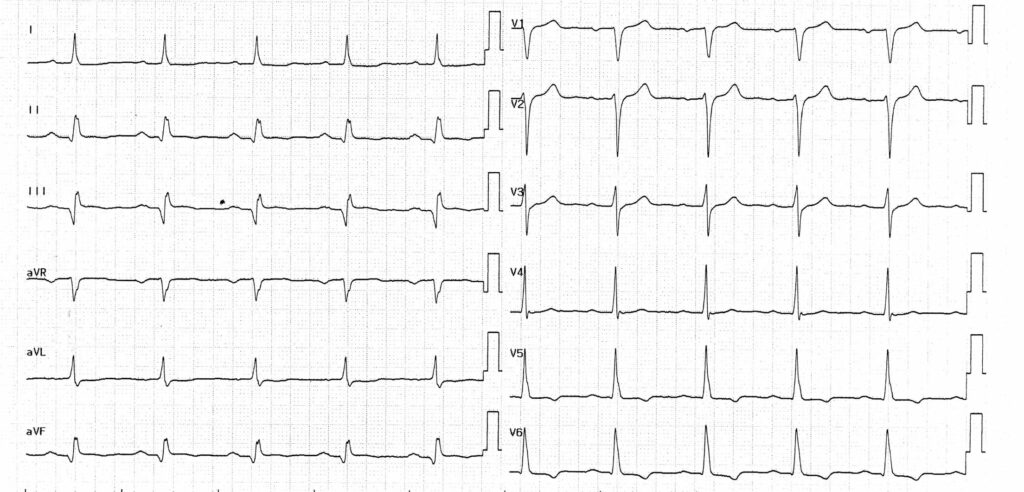

Description tracé

Tracé enregistré le lendemain de la réduction de la tachycardie; rythme sinusal, bloc auriculo-ventriculaire du premier degré; séquelle de nécrose inférieure (onde q en DII, DIII, aVF); bloc pariétal avec QRS modérément élargi (122 ms);